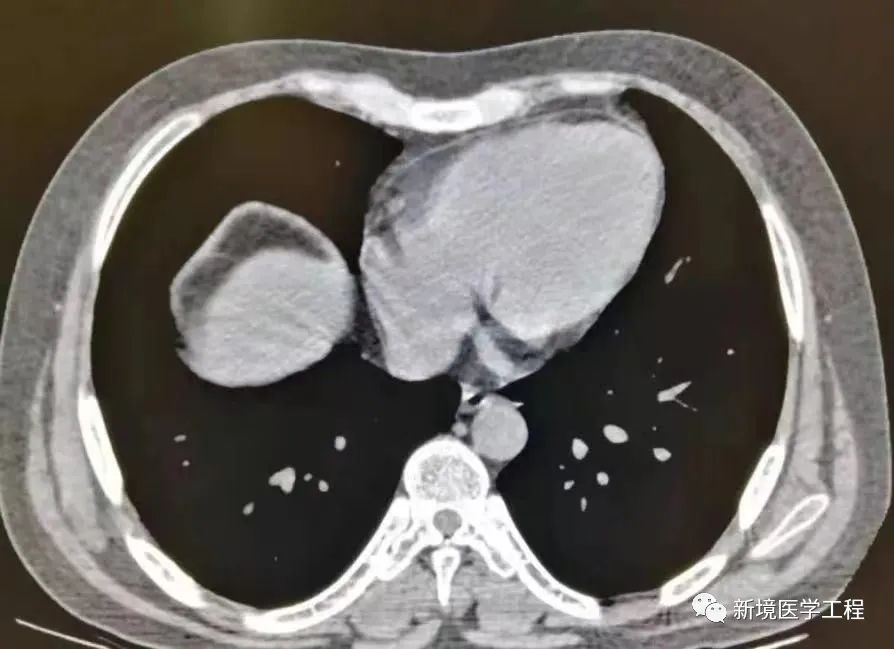

2.2 「胸腹部运动伪影」

【产生原因】

患者在时未憋住气导致的膈肌运动轮廓伪影

【解决办法】